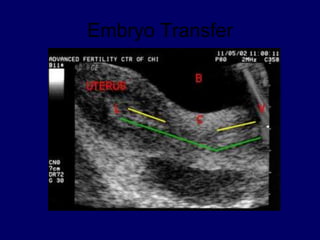

Embryo Transfer